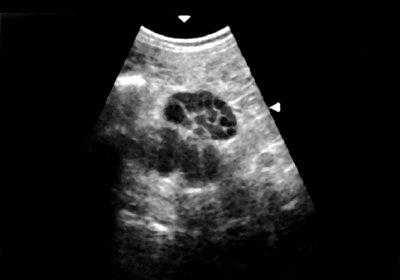

В диагностике мультилокулярных кист ценные сведения можно получить при помощи ультразвукового исследования (УЗИ). По данным разных авторов, достоверность УЗИ в диагностике данной патологии составляет от 94 до 97,3% [1, 8, 9, 11-13]. Эхографически мультилокулярная киста визуализируется в виде многокамерного жидкостного образования округлой формы, расположенного в одном из полюсов почки, с множеством перегородок, как правило, с отложением извести, с четкими ровными контурами и дорсальным усилением эхо-сигнала (рис. 2) [1-3, 6, 8, 9, 12, 14]. Цветное допплеровское картирование (ЦДК) увеличивает чувствительность УЗИ, так как улучшает визуализацию областей с атипичной сосудистой архитектоникой и снижением васкуляризации. При допплерографии отмечаются неспецифические изменения почечного кровотока в виде повышения пульсационного индекса и индекса резистентности, особенно выраженных в сосудах, огибающих образование. Если при УЗИ обнаруживаются утолщение перегородок кист или солидные структуры, в которых при ЦДК регистрируются сосуды, это может быть признаком малигнизации [11, 13, 15-19].

Эхонегативное многокамерное образование неправильной формы, с неровными стенками. Большое количество тонких перегородок в полости образования.

Ультразвуковое исследование. Почки расположены типично, в размерах не изменены, контуры ровные, четкие, подвижность сохранена, полостная система не расширена. Мочеточники не визуализируются. Конкрементов не выявлено. В нижнем полюсе правой почки визуализируется эхонегативное многокамерное образование диаметром до 30 мм, с большим количеством перегородок внутри и единичным кальцинатом.

Заключение: Сложная киста нижнего полюса правой почки (рис. 4).

Округлое кистозное образование с множеством перегородок в полости образования и единичным кальцинатом.